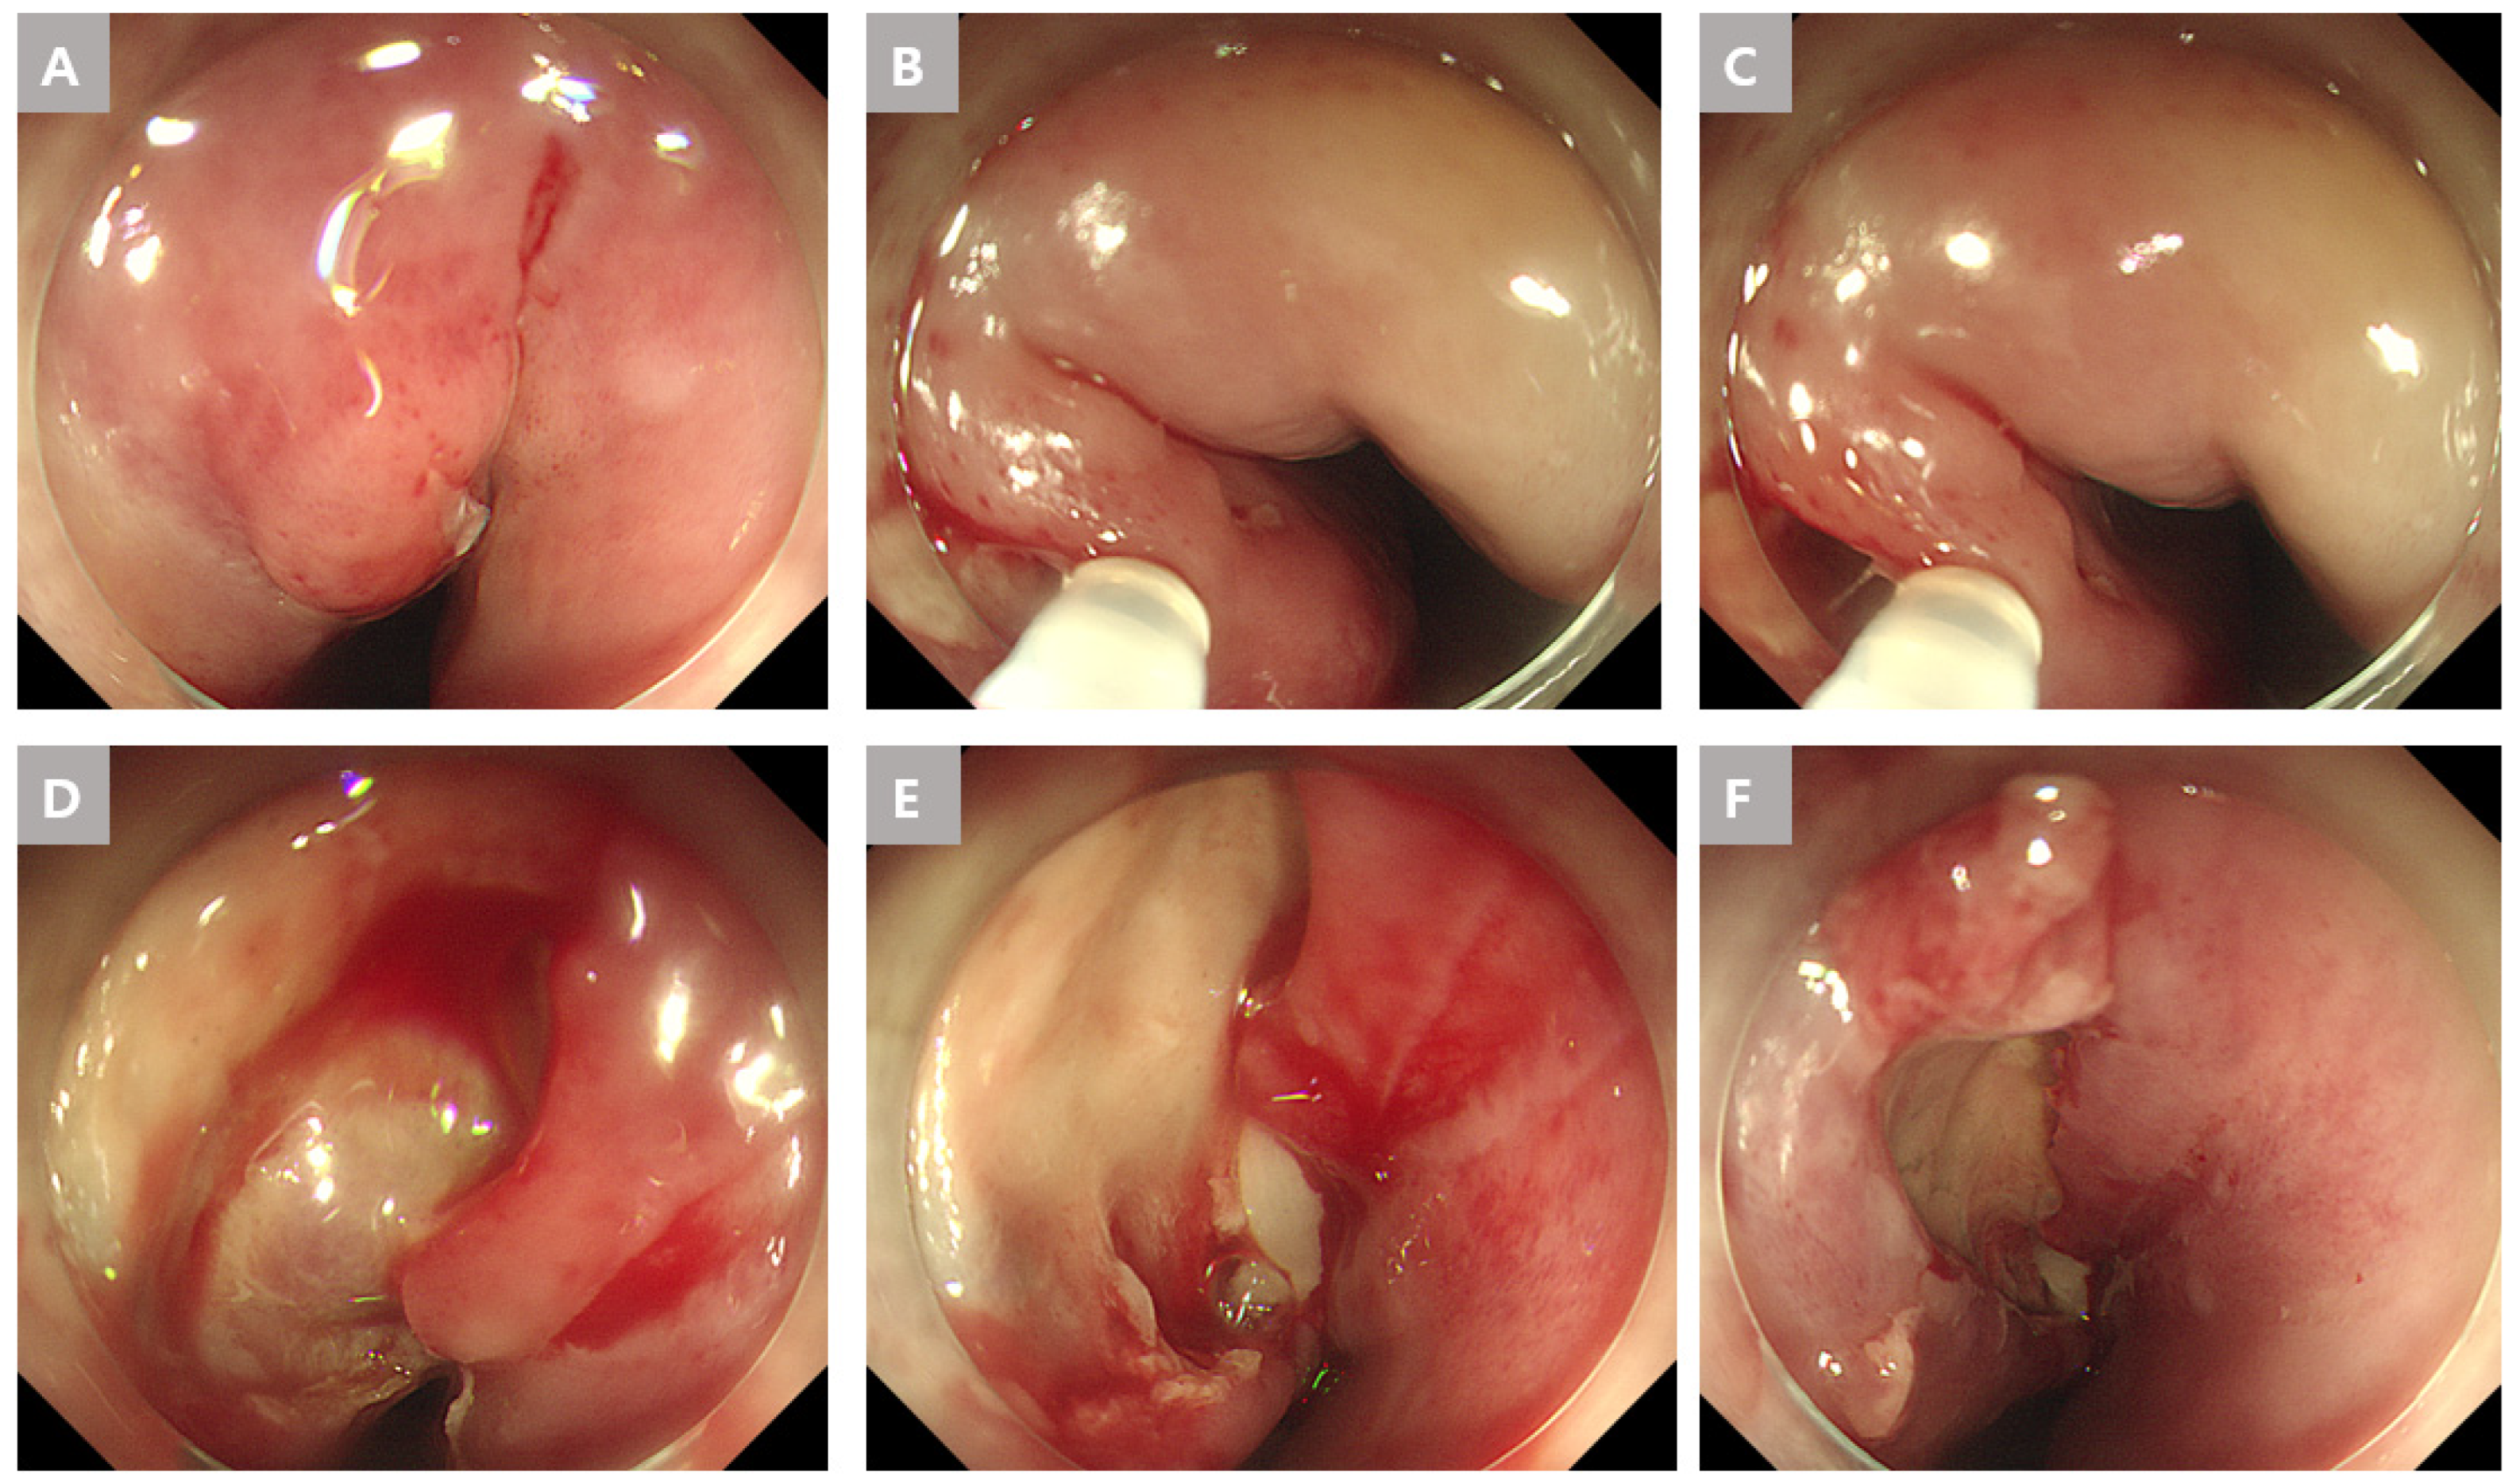

Laboratory tests showed a white blood cell count of 21,670 μL (normal range: 4500–11,000 μL) and elevated C-reactive protein (CRP, >300 mg/L, normal range: 0–5 mg/L). A chest CT performed on the day of admission to the emergency room revealed distal esophageal perforation abscess formation and a pneumomediastinum (Figure 3(A-1,A-2)). After starting broad-spectrum antibiotics, the patient underwent an emergency surgical operation (mediastinotomy via minithoracotomy), performed on the lower part of the thoracic esophagus, and a pus culture and massive irrigation were performed. Streptococcus anginosus, Streptococcus mitis, and Streptococcus oralis were cultured in the results of staining and culture performed on pus collected during surgery. However, no bacteria were identified in the blood culture.

On day three of hospitalization, a chest and abdomen CT scan showed distal esophageal perforation with abscess and infectious fluid in the posterior mediastinum and lesser sac. The upper endoscopy showed a small mucosal opening that appeared to be punctured up to the muscle layer at the 40 cm from the UI (Figure 4A). Percutaneous abscess drainage (PCD) insertion was performed for fluid collection at the Lt. pleural space.

One week later, a chest CT scan showed an increased amount of fluid collection in the lesser sac and greater omentum (Figure 3(B-1,B-2)). On the follow up upper endoscopy, continuous drainage of whitish exudate at the perforation site was observed (Figure 4B). PCD insertion was performed for fluid collection at the Lt. aspect of the stomach and peritoneal space.

After two weeks of hospitalization, a chest CT scan showed decreased fluid collection in the lower paraesophageal area and remnant fluid collection in the lesser omentum and pelvic cavity (Figure 3(C-1,C-2)). On the follow up upper endoscopy, the previously observed orifice was not visible (Figure 4C). Esophagography was performed prior to feeding, and there was no leakage.

After three weeks of hospitalization, the follow up chest and abdomen CT scan showed nearly disappeared fluid collection in the lower paraesophageal area and decreased remnant fluid collection in the lesser omentum and pelvic cavity. The patient was discharged on day 28 without any other complications. A final follow up CT scan was performed two weeks after discharge, and no abscess cavity was observed in the chest or abdominal cavity.

Figure 3. Image findings of the distal esophageal perforation with descending peritoneal abscess due to a fish bone foreign body in Case 2. (A-1,A-2) A distal esophageal perforation abscess formation and pneumomediastinum was seen by computer tomography (CT) scan. (B-1,B-2) Increase in the amount of fluid collection in the lesser sac and greater omentum was revealed by the CT scan 1 week later. (C-1,C-2) Nearly disappeared fluid collection in the lower para esophageal area and lesser omentum by the CT scan.